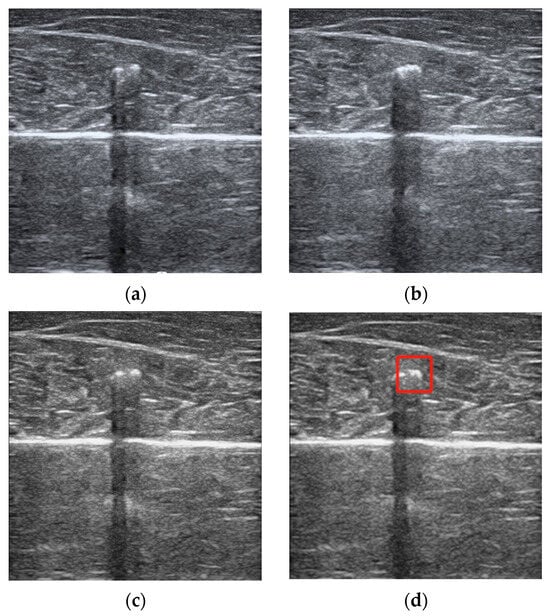

The ultrasound video file, recorded in .AVI format with a duration of 8 min and a frame rate of 30 frames per second, was processed along with the corresponding temperature-probe-recorded heating curve. The images from each frame of the video file were captured, and the time dimensions of the ultrasound images were fused to align the image frequency with the temperature sampling frequency (Figure 2c). Subsequently, each image underwent mean filtering [] to remove speckle noise. A region of interest measuring 64 × 64 pixels, centered around the temperature probe, was selected for further processing, as indicated by the red box in Figure 2d.

Figure 2.

(a) ultrasound image before heating; (b) ultrasound image after heating; (c) image fused along the time dimension; (d) image after mean filtering.